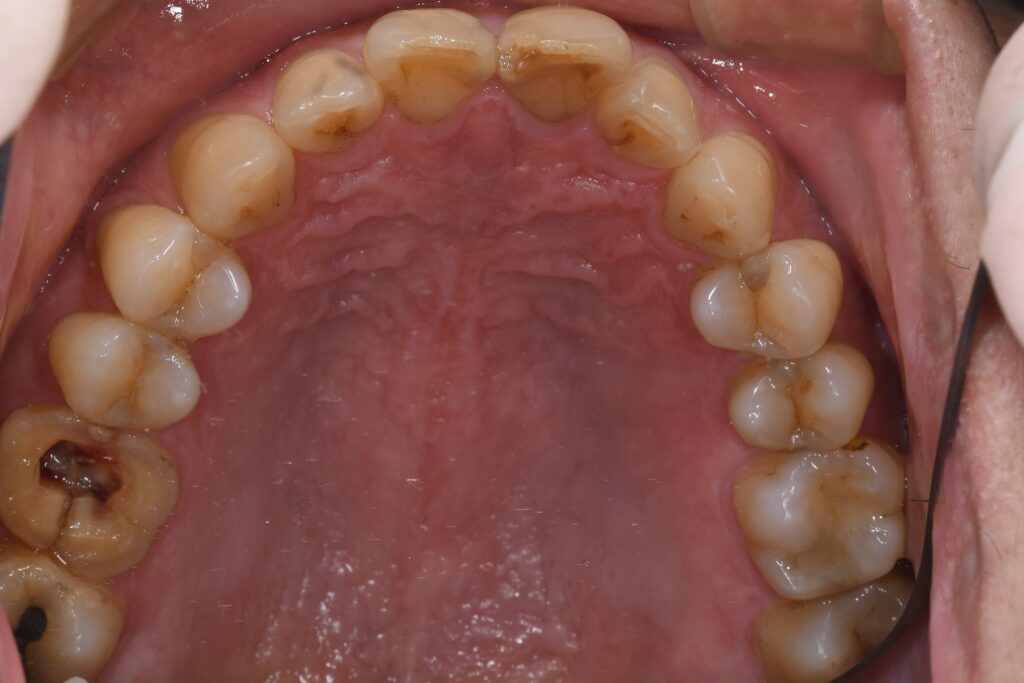

年齢 38歳 性別 女性 初診日 2021年11月 主訴 歯がグラグラする 治療内容 インプラント・セラミック修復 治療期間 1年2ヶ月 治療費用 約85万円 治療経過 前歯の差し歯がグラグラするとのことで来院された。 左の前歯は歯根が折れており、保存が難しい状態で…